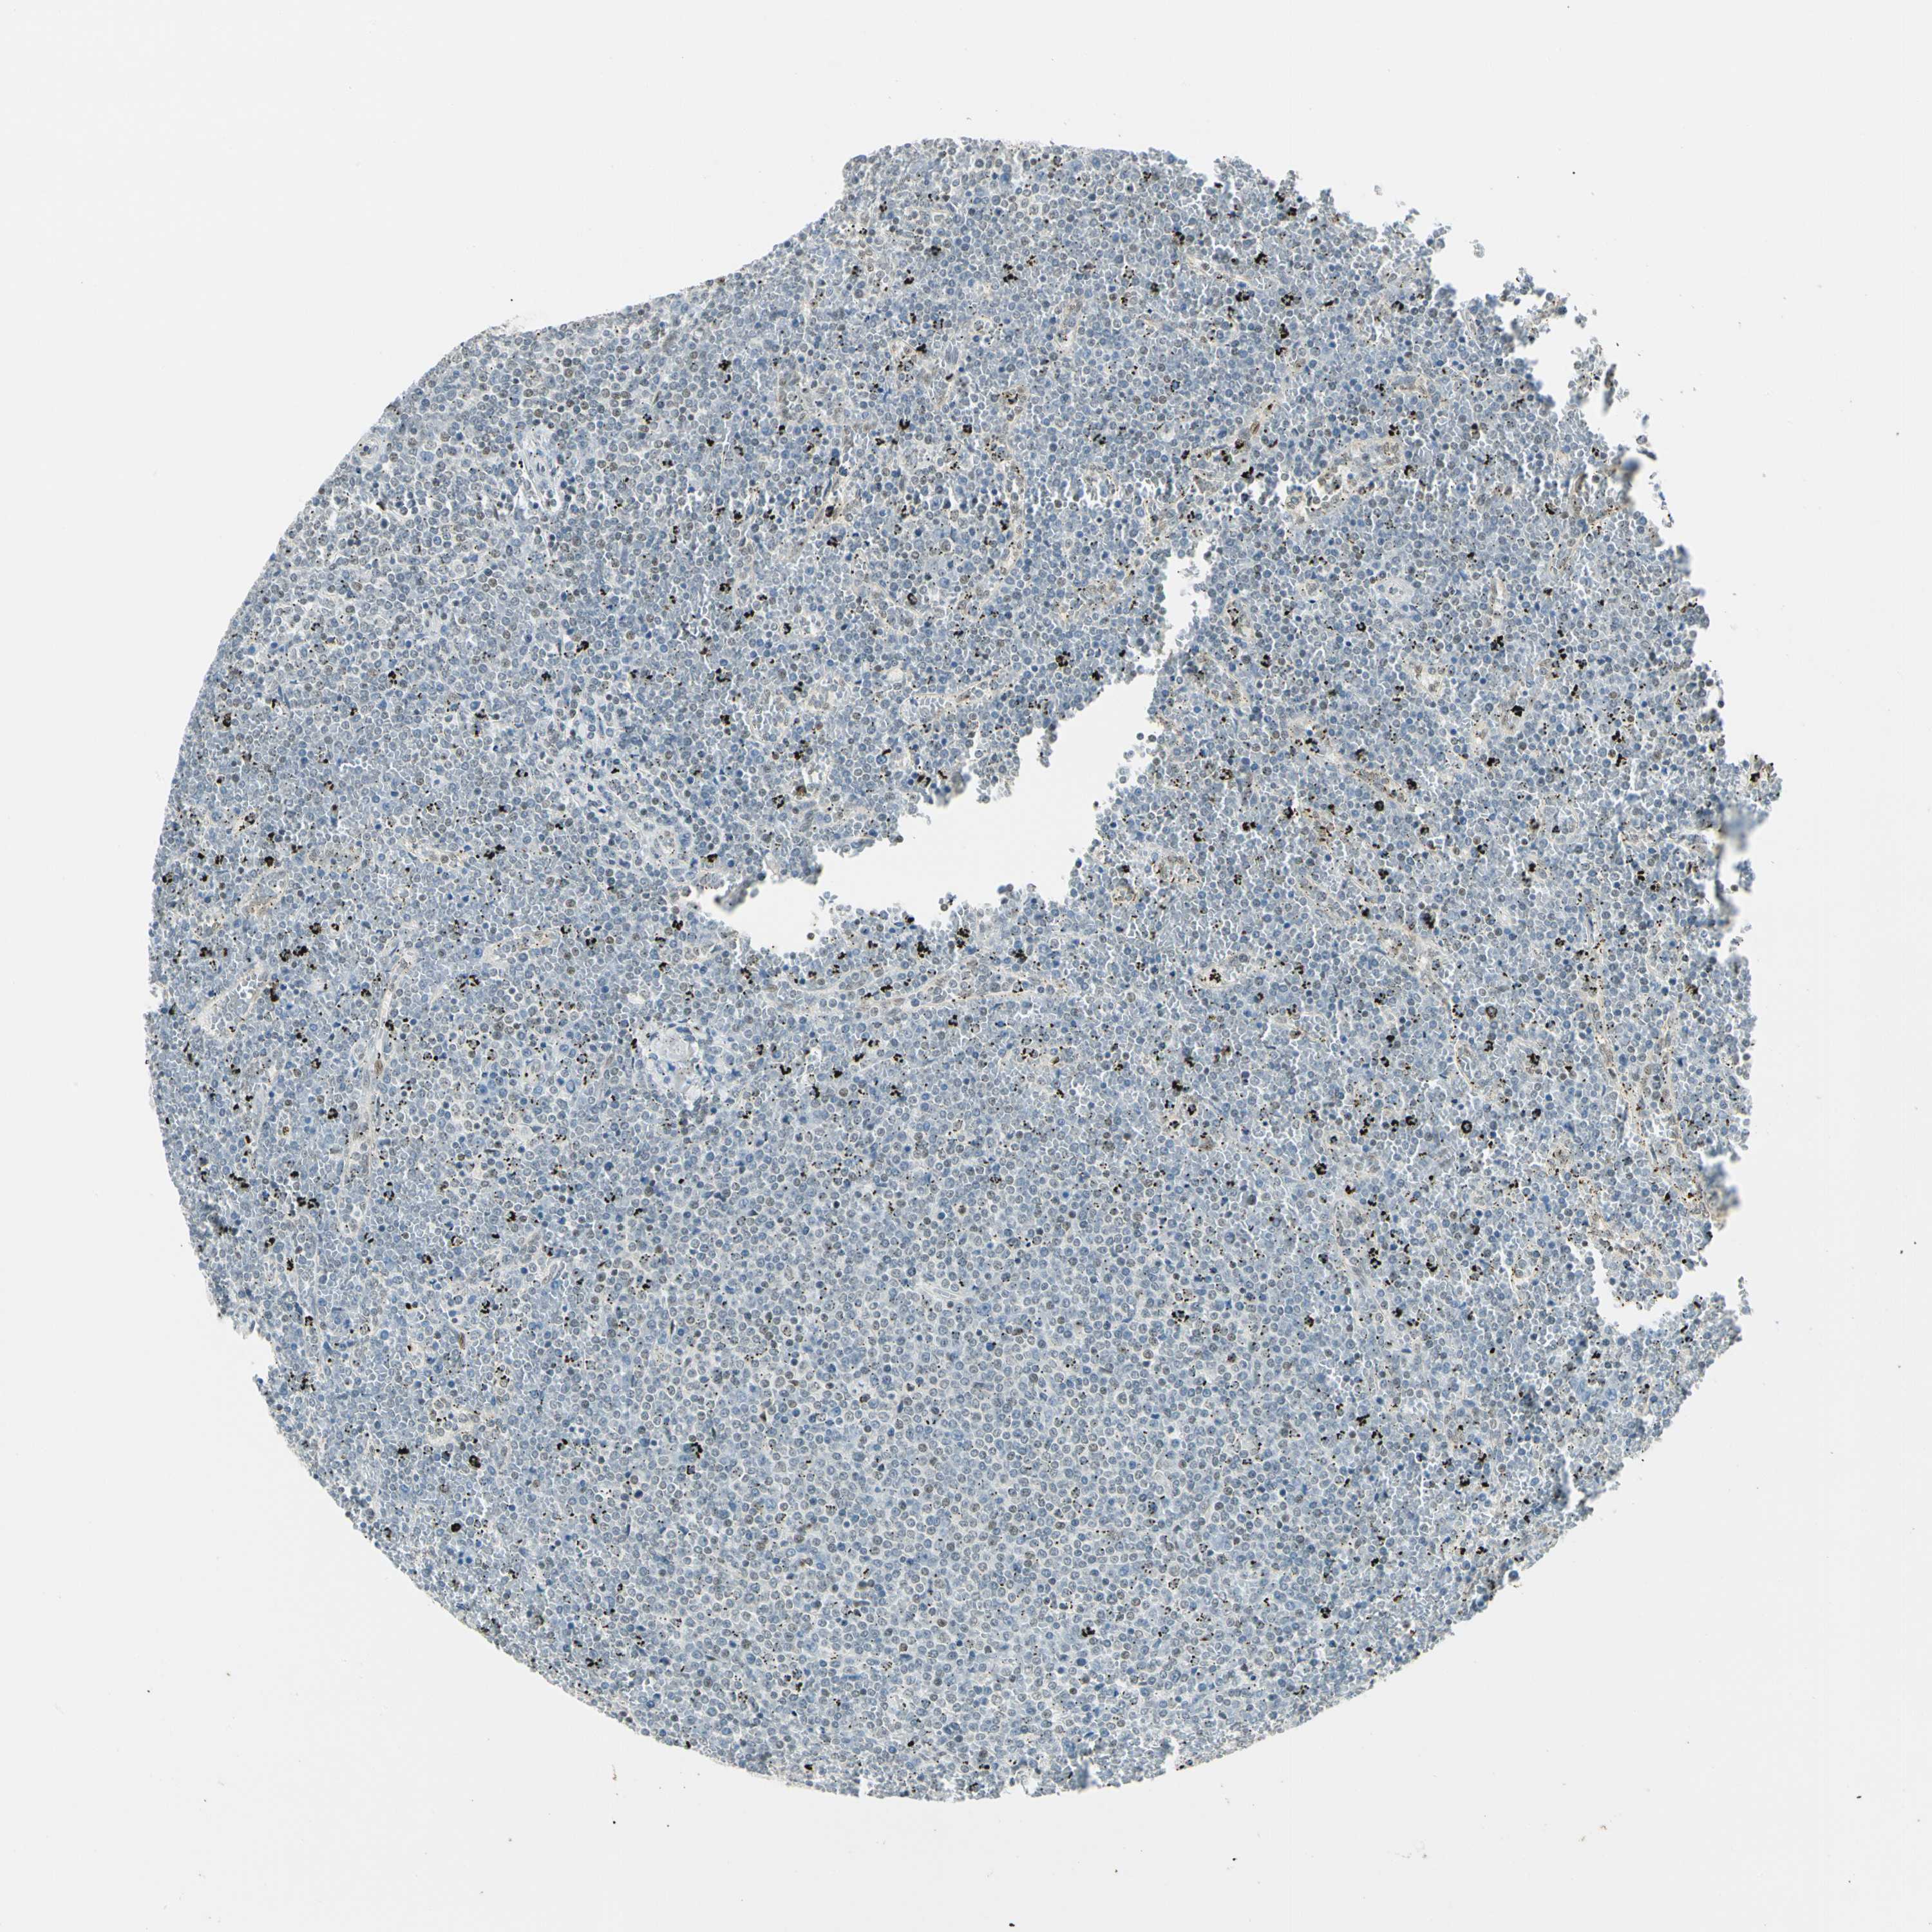

CANCER LYMPHOMA Show tissue menu

LYMPHOMA - Protein expressioni

A mouse-over function shows sample information and annotation data. Click on an image to view it in a full screen mode. Samples can be filtered based on level of antibody staining by selecting one or several of the following categories: high, medium, low and not detected. The assay and annotation is described here.

Each image is clickable and will lead to virtual microscopy that enables deeper exploration of all samples and also displays staining intensity scores, fraction scores and subcellular localization as well as patient and tissue information for each sample.

Antibody HPA007187

Staining

High

Medium

Low

Not detected

Intensity

Strong

Moderate

Weak

Negative

Quantity

>75%

75%-25%

<25%

None

Location

Nuclear

Cytoplasmic/membranous

Cytoplasmic/membranous,nuclear

Hodgkin's disease, NOS

Malignant lymphoma, non-Hodgkin's type, Low grade

Malignant lymphoma, non-Hodgkin's type, High grade